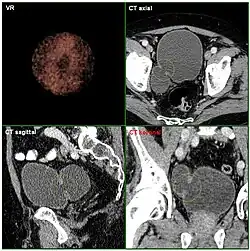

Die Harnblase ist bildgebend mittels Sonographie, Röntgen, Kernspintomographie, Computertomographie und endoskopisch darstellbar. Bildgebung der ersten Wahl sind die Verfahren ohne Röntgenstrahlung, zumeist die Sonographie.

Die Röntgendarstellung der Harnblase heißt Zystographie. Da Weichteile auf Röntgenbildern prinzipiell kaum erkennbar sind, wird beispielsweise zur Füllung triiodiertes Kontrastmittel verwendet. Diese Technik kann so auch Blasendivertikel, Tumoren und nicht röntgenkontrastgebende Fremdkörper sichtbar machen, Hauptanwendung eines Miktionszystourethrogrammes ist die Suche nach einem Reflux, VUR.